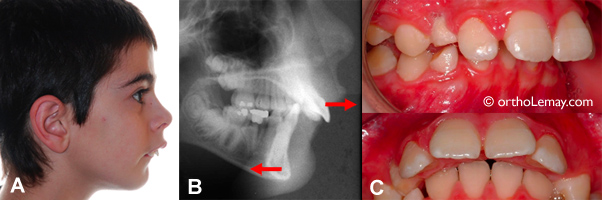

Les malocclusions Classe 2 division 1 sont principalement dues à une mâchoire intérieure reculée. Lorsque les incisives supérieures sont aussi avancées, ceci augmente l’écart entre les deux mâchoires. (A) Garçon de 12 ans avec mandibule reculée. (B) la radiographie montre la mandibule reculée et les incisives supérieures avancées.